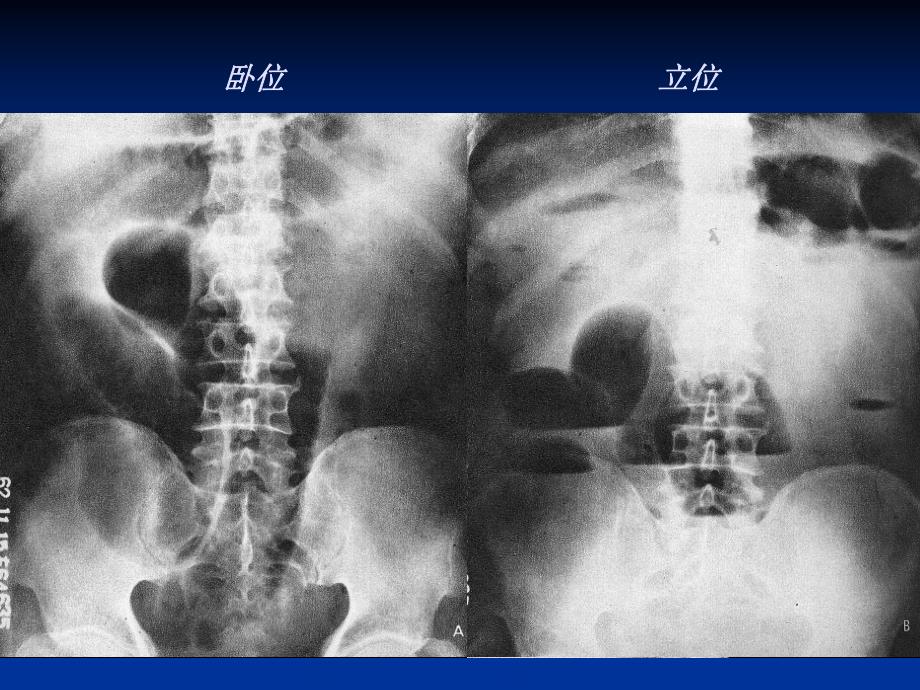

1、卧位卧位立位立位第二节第二节 胃肠道穿孔胃肠道穿孔(一)病因 胃肠道穿孔常继发于胃肠道的溃疡、创伤破裂、炎症及肿瘤,以胃、十二指肠溃疡最常见。(二)(二)X线表现线表现 主要表现为腹腔内有游离气体影,称主要表现为腹腔内有游离气体影,称气腹,但穿孔不能定位是来源胃,还是肠气腹,但穿孔不能定位是来源胃,还是肠道。道。X线平片或透视表现为两膈面下可见线平片或透视表现为两膈面下可见新月状、眉弓状透亮影。新月状、眉弓状透亮影。正常腹腔内,脏,壁层腹膜之间无气体存留。若因某种病因导正常腹腔内,脏,壁层腹膜之间无气体存留。若因某种病因导致腹内积气且随体位改变而游动,该气体则称游离气腹致腹内积气且随体位改变而

2、游动,该气体则称游离气腹。站立位表现为膈站立位表现为膈下游离气体:新月形低密度气体影。下游离气体:新月形低密度气体影。(三)鉴别诊断(三)鉴别诊断1子宫输卵管通气术后2腹部手术后3人工气腹第三节第三节 肠梗阻肠梗阻 病因 肠梗阻多是由肠粘连、扭转、肿瘤和寄生虫(如蛔虫)等引起,其中肠粘连最常见。分型 三型:单纯性、绞窄性和麻痹性肠梗阻影像检查的目的 主要是明确梗阻的类型、梗阻的部位和原因。X线表现 主要的X线表现为肠管积气、扩张及肠腔内的气液平面(一)单纯性肠梗阻(一)单纯性肠梗阻X线表现1 小肠扩张积气(3cm)。卧位检查时积气的肠管常在中上腹,肠管表现为平行排列、相互靠拢,显示呈像鱼肋样或

3、弹簧样改变;肠管皱襞减少。2 肠腔内积液。立位检查时肠腔内出现多个高低不等、长短不一的呈阶梯状排列的气液平面。3 梗阻远端肠腔内的气体减少或消失。梗阻发生3-6小时后,出现梗阻近端肠曲扩张、积气(红箭头)、肠内有高低不等的阶梯状气液平面(蓝箭头)。梗阻发生3-6小时后,出现梗阻近端肠曲扩张、积气(红箭头)、肠内有高低不等的阶梯状气液平面(蓝箭头)。根据积气扩张的肠管形态可判断梗阻的大体部位,空肠呈鱼肋状,回肠呈光滑管状,结肠可见结肠袋。空肠段以上梗阻为高位肠梗阻,回肠段以下梗阻为低位肠梗阻。肠管扩张、积气、积液,并见结肠袋,结肠梗阻的特点是梗阻近段的扩张较远离端轻。根据积气扩张的肠管形态可判断